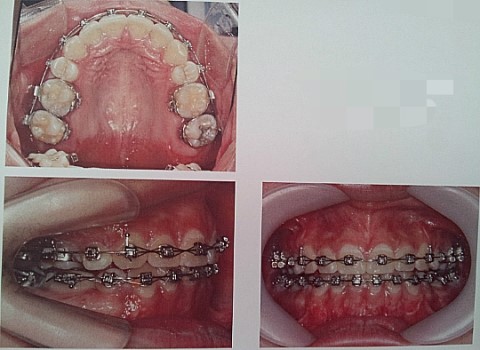

상악입안사진

보이실지 모르겠습니다만 하악 치열라인입니다.. 어금니들이 안쪽으로 누워있어요...

가장불만인 윗입술인중과 아랫입술의 돌출차이입니다 ㅠㅠ